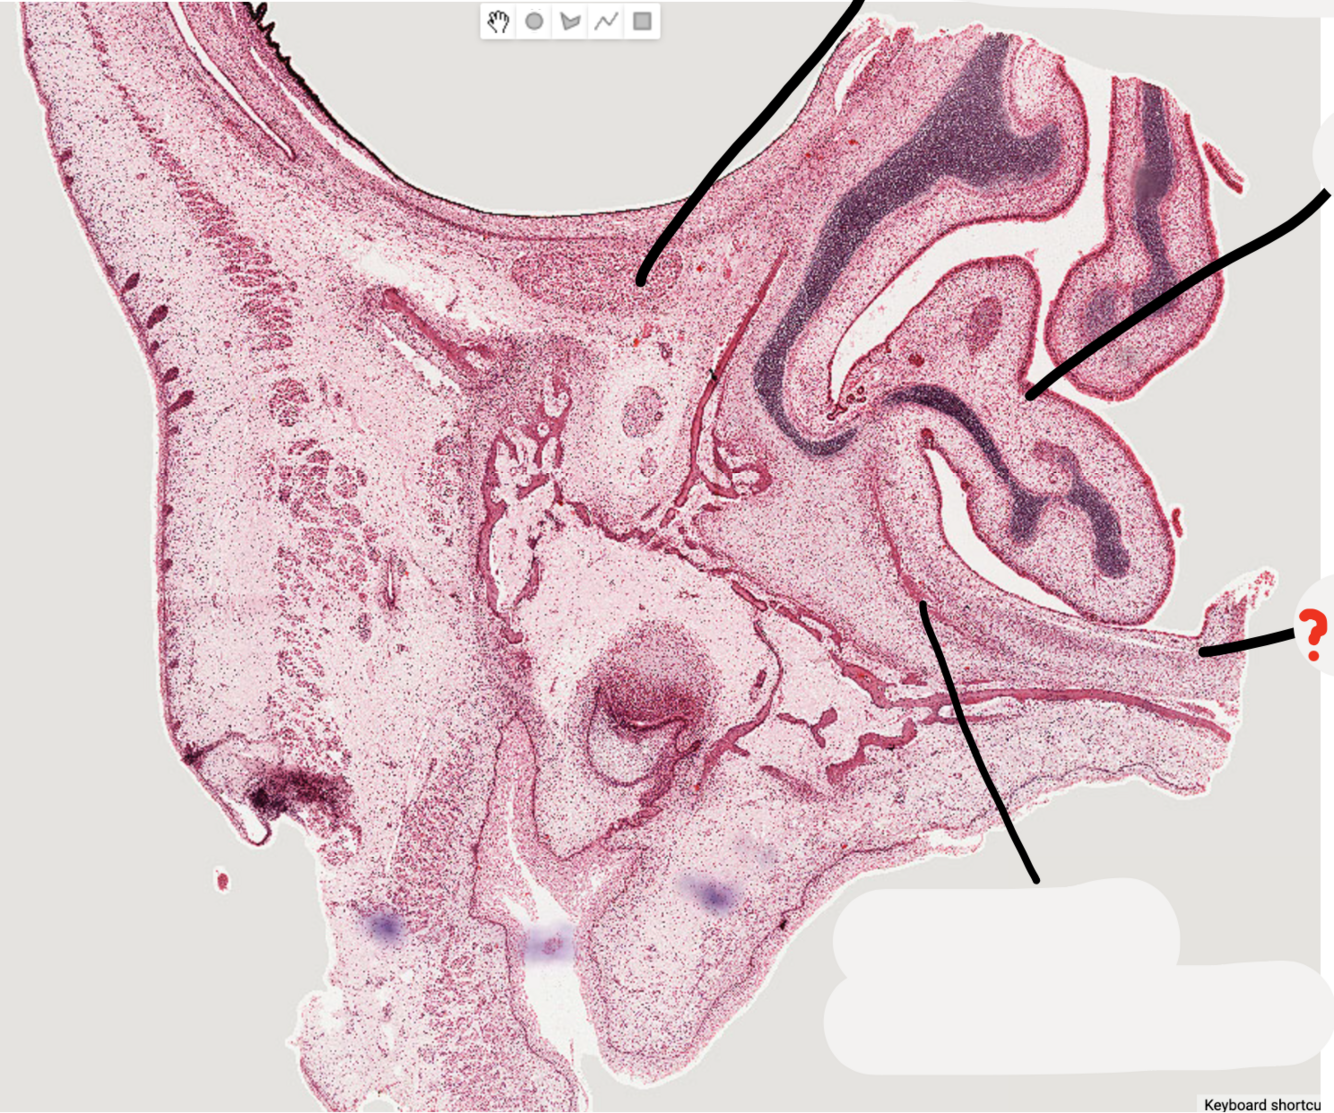

9

Q

A

infraorbital nerve

10

inferior nasal concha

11

palatal process of developing maxillary bone

12

alveolus of developing maxillary bone